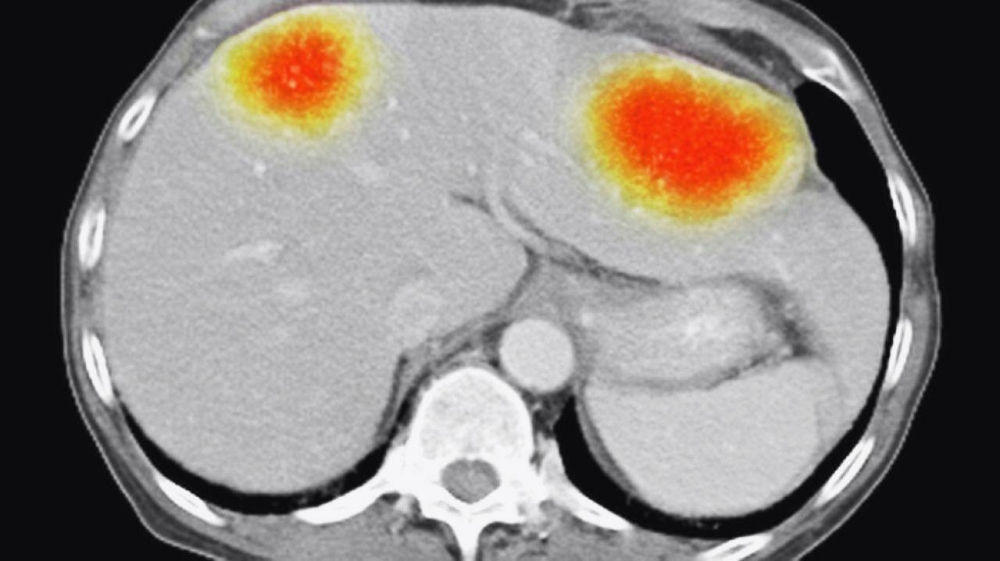

تمكَّن باحثون من استخدام جزيئات صغيرة من الذهب، مشحونة كهربائياً، لخداع الخلايا في أحد أكثر أنواع السرطان فتكاً كي تقوم بتدمير نفسها، ويأمل هؤلاء أن يصبح العلاج متاحاً يوماً ما على شكل رذاذ.

وقام فريق العلماء، من جامعة نوتنغهام، بقيادة الدكتور فرانكي روسون؛ بحسب تقرير نشره موقع (روسيا اليوم)، بتسخير قوة bio-antenna تُميت الخلايا بشكل مبرمج، (خلايا الورم الأرومي الدبقي). ويزعم العلماء أن هذا هو أول نهج علاجي كمي، يُظهر أنه يمكن القضاء على السرطان عن طريق إجراء تغييرات في بيولوجيا الخلايا على المستوى الكمي.